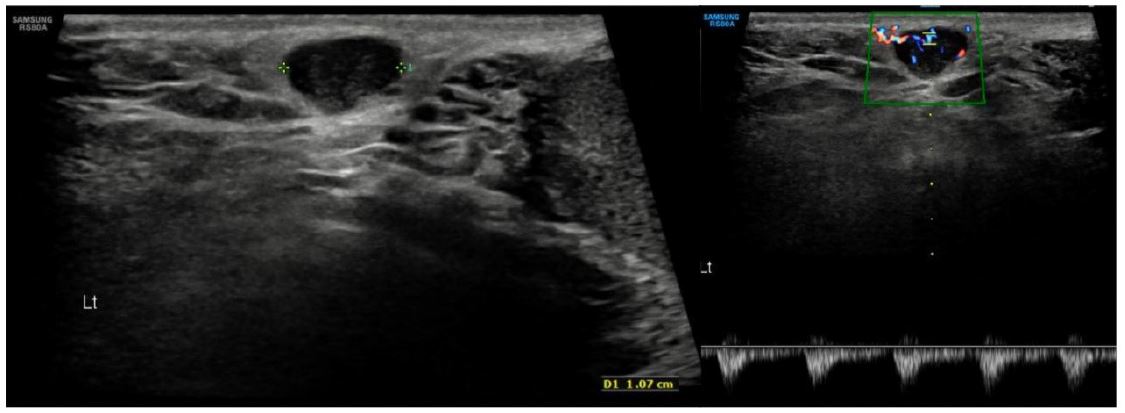

A 45-year-old male, former smoker (2 package index year) with no significant medical history, presented to Internal Medicine in May 2023 with a 4-month history of persistent dry cough and pleuritic chest pain. A chest X-ray revealed an opacity in the right lower lobe, initially of uncertain inflammatory or infectious etiology. The patient also reported a left scrotal lesion, noticed months earlier, presumed to be a lipoma and awaiting excision. A left testicular ultrasound was performed, revealing an oval-shaped lesion measuring approximately 11×5 mm (Figure 1).

Figure 1: Adjacent to the left inguinal canal, in contact with its vasculature, an oval-shaped lesion measuring approximately 11×5 mm is identified. Color Doppler reveals vascular flow; however, the lesion remains nonspecific with this modality and may correspond to a lymph node.